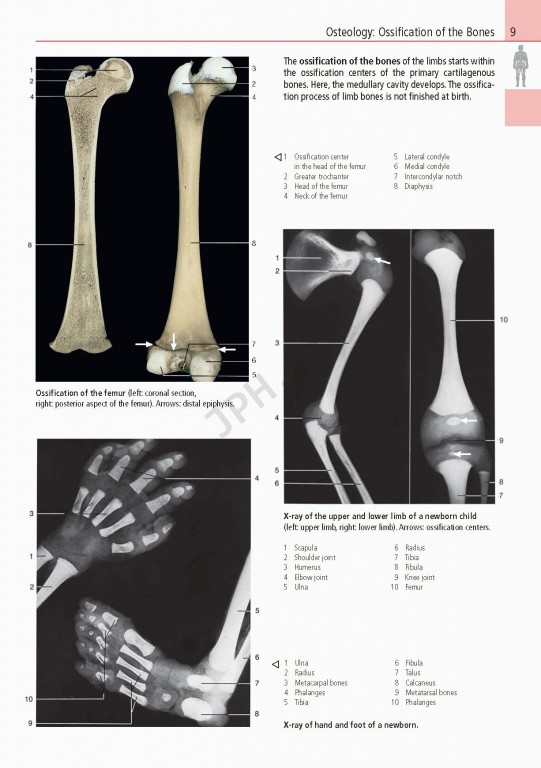

ویراست هشتم کتاب Rohen Atas Of Anatomy 2015 با استفاده از عکس‌های برجسته و کاملا رنگی از شکاف‌های واقعی جسد همراه با نقاشی‌های شماتیک و تصاویر تشخیصی ساختارهای آناتومیک را به صورت واقعی تر از تصاویر موجود در اطلس‌های سنتی به تصویر می کشد.

Prepare for the dissection lab and operating room with Anatomy: A Photographic Atlas , 8e. Featuring outstanding full-color photographs of actual cadaver dissections with accompanying schematic drawings and diagnostic images, this proven text depicts anatomic structures more realistically than illustrations in traditional atlases. Chapters are organized by region in the order of a typical dissection with each chapter presenting topographical anatomical structures in a systemic manner.

Authentic photographic reproduction of colors, structures, and spatial dimensions as seen in the dissection lab and on the operating table help you develop an understanding of the anatomy of the human body.

Clinical cases and over 1,200 images enhance your understanding.

عالی بود 😍😍😍بخصوص تصاویر رادیوگرافی هم داره عالیترش کرده